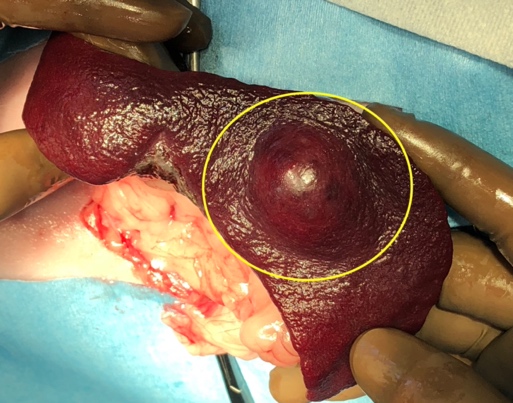

脾臓腫瘍

腫瘍が大きくなることでお腹の腫れなどを認めることがあります。また腫瘍が破裂することにより、腫瘍からの出血量によっては急性の虚脱や劇的な症状を伴うこともあります。

犬では血管肉腫が最も多い腫瘍であり、ジャーマンシェパードやレトリーバー種で発生が多いと言われています。

猫では脾臓の腫瘍は犬ほど多くはないが、猫では脾臓疾患の15%を肥満細胞腫という腫瘍が占めます。